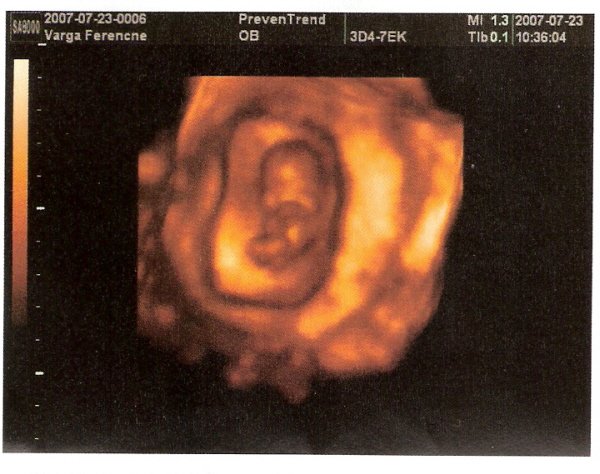

Annyira örülök a jó eredmény miatt, na meg persze az miatt is, hogy kislány a drága.